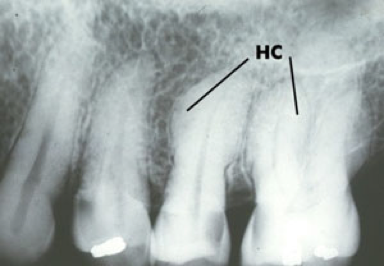

Taurodontisme : le taurodontisme est caractérisé par des dents dont la chambre pulpaire s’étend bien au delà du collet : il n’y a donc pas d’étranglement au collet, comme des dents d’herbivores.

Taurodontisme (quizlet.com).